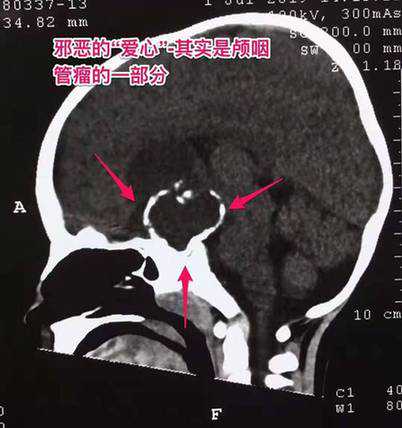

周忠清主任接诊时发现,果果身材较同龄矮10公分左右,同时双眼内斜视。从影像资料来看,颅内鞍上有一“爱心”状的信号影,直径长约6厘米大小(有兵乓球大小),病灶内可见明显钙化,考虑颅咽管瘤可能性非常大。

脑部深处藏了个“爱心”,但是却很“邪恶”。周忠清介绍,颅咽管瘤是一种先天性肿瘤,它起源于胚胎时期颅咽管的残余组织,是一种良性肿瘤。颅咽管瘤占颅内肿瘤2.5%-4%,任何年龄都可发病,人群年发生率为1.3/100万。虽然颅咽管瘤是一种良性肿瘤,但儿童发病率较高,危害极大,影响儿童的生长发育,也可以影响患者的视力,严重时可导致失明,也可以出现脑积水,严重时可危及患者的生命。肿瘤生长得越大,手术危险就越大,效果也越差,因此应该尽早治疗。